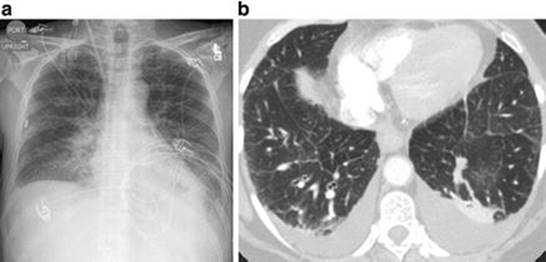

Pulmonary Edema

Pulmonary edema can be visualized on chest radiograph as diffuse interstitial opacities, which may coalesce into consolidations; the periphery is often spared in cardiogenic pulmonary edema (Fig. 15.3) [13].

Fig. 15.3

Pulmonary edema . (a) AP chest radiograph shows pulmonary vascular indistinctness, diffuse opacification, and septal thickening. Blunting of the costophrenic angles indicates bilateral pleural effusions. (b) Axial CT image through the lower lobes, demonstrating interlobular septal thickening, ground-glass opacities, and small bilateral pleural effusions (Reprinted from Bentz and Primack [11], with permission from Elsevier)